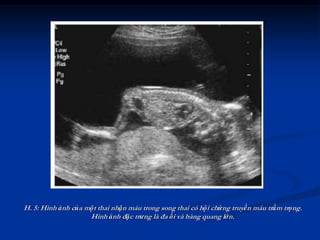

thể bị phù thai (H. 5).

H. 5: Hình ảnh của một thai nhận máu trong song thai có hội chứng truyền máu trầm trọng.

Hình ảnh đặc trưng là đa ối và bàng quang lớn.